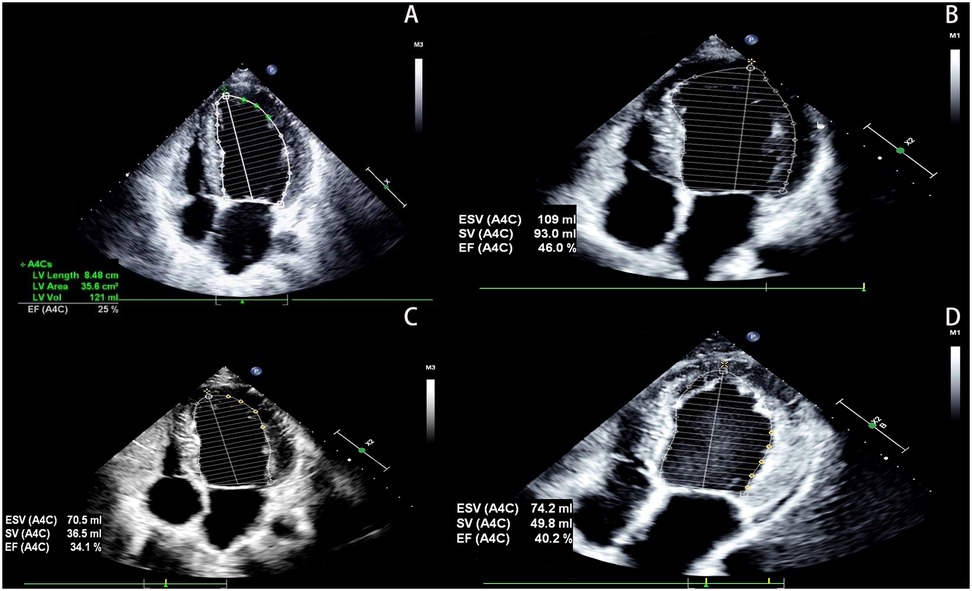

The proband was a 33-year-old man who presented to the outpatient department in May 2022 due to a 12-day history of shortness of breath. He had no history of hypertension, diabetes, hyperlipidemia, or other diseases, and denied smoking, drug use, or alcohol abuse. There was no family history of cardiac disease or sudden cardiac death at a young age. His blood pressure was 125/79 mmHg with a heart rate of 79 bpm. Electrocardiography (EKG) showed sinus rhythm, incomplete left bundle branch block, and left anterior fascicular block. Chest CT scan revealed left ventricular enlargement. Echocardiography demonstrated: left ventricular end-diastolic diameter (LVED) of 68 mm, left atrial diameter (LAD) of 46 mm, right atrial diameter (RAD) of 36 mm, right ventricular end-diastolic diameter (RVD) of 32 mm, interventricular septal thickness at diastole (IVSd) of 9 mm, left ventricular posterior wall dimensions (LVPWd) of 9 mm, and left ventricular ejection fraction (LVEF) of 25% (Figure 1A). The echocardiogram also showed myocardial thinning with non-compacted layer thickening. The patient was diagnosed with heart failure and treated with digoxin, furosemide, spironolactone, and sacubitril/valsartan. After one week without symptom improvement, he was hospitalized.

Figure 1

The patient's echocardiography results. (A) Show the echocardiographic result of the patient's heart at hospitalization (2022). (B) Show the echocardiographic result of the patient's heart at 1 year follow-up (2023). (C) Show the echocardiographic result of the patient's heart at 2 years after discharge, post-infection (2024). (D) Show the echocardiographic result of the patient's heart at 3 years follow-up (2025).

Based on these findings, DCM was diagnosed. Although genetic testing was recommended for further clarification, the patient declined due to financial constraints. After 6 days of treatment with spironolactone, metoprolol, sacubitril/valsartan, and recombinant human brain natriuretic peptide, his condition improved. At discharge, he was prescribed spironolactone, metoprolol, and sacubitril/valsartan. Follow-up showed stable symptoms, and one year later, echocardiography revealed LVED of 60 mm, LAD of 47 mm, and LVEF of 46% (Figure 1B). Vericiguat was added to his medication regimen.

Two years after initial presentation (March 2024), the patient was readmitted for worsening dyspnea following infection. Echocardiography showed: LVED 57 mm, LAD 33 mm, RAD 31 mm, RVD 31 mm, and LVEF 34% (Figure 1C). He responded well to intravenous recombinant human brain natriuretic peptide and was discharged after 4 days. He maintained treatment with spironolactone, metoprolol, sacubitril/valsartan, and vericiguat, with regular follow-up showing stable NYHA class II symptoms, improved dyspnea, and increased exercise tolerance. At the 3-year follow-up, echocardiography demonstrated: LVED 58 mm, LAD 36 mm, RAD 35 mm, RVD 33 mm, and LVEF 40% (Figure 1D). Laboratory tests showed persistent microscopic hematuria (+) without proteinuria and normal renal function (Clinical parameters shows in Table 1).